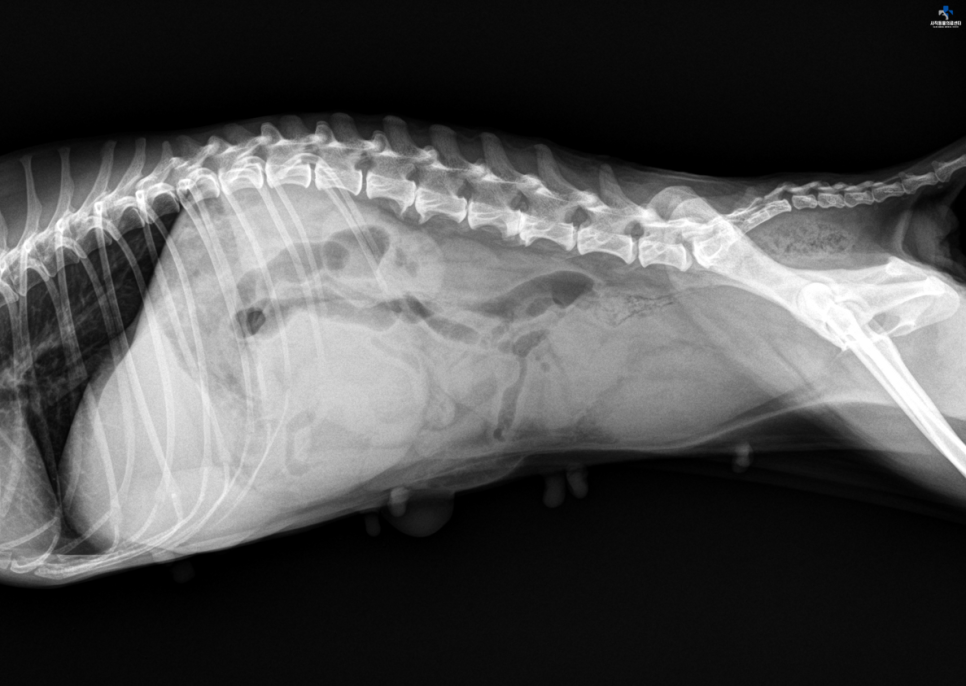

x선상에서 복강 내 mass 음영과 자궁확장을 볼 수 있으며,

US에서 왼쪽 난소 mass를 확인했습니다.03. 진단 및 치료계획위 결과를 종합해 본 결과 자녀의 자궁축농증 및 난소종양, 제대탈장을 진단하고 보호자와 상담 후 난소자궁적출술(OHE) 및 탈장교정을 시행하기로 하였습니다.04. 수술에 들어가기 전 2차 감염에 대비하여 주위의 털을 모두 사모한 후 소독하고 수술을 시작했습니다.